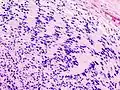

| Micrograph of a schwannoma showing both a cellular Antoni A area (top) and a loose paucicellular Antoni B area (bottom). HE stain. | |

Antoni A area of schwannoma with Verocay bodies (one annotated by circle) -